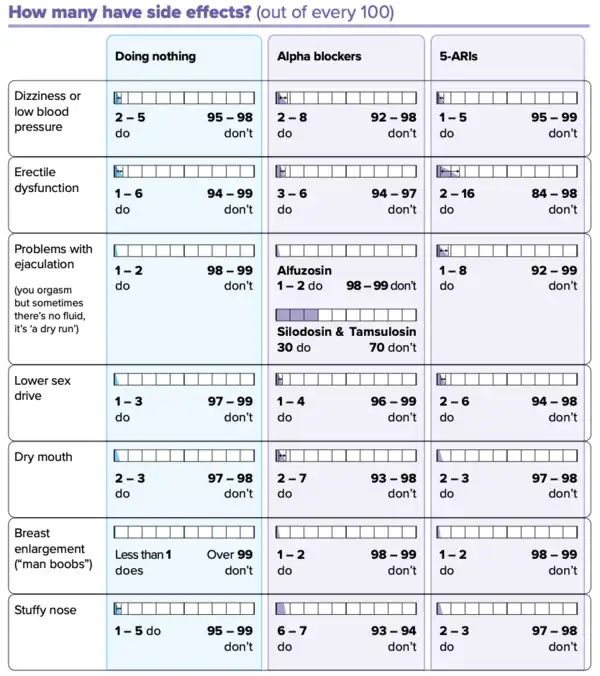

Alpha-blockers

Selective α1-blockers are the most common choice for initial therapy.[65][66][67] They include alfuzosin,[68][69] doxazosin,[70] silodosin, tamsulosin, terazosin, and naftopidil.[58] They have a small to moderate benefit at improving symptoms.[71][58][72] Selective alpha-1 blockers are similar in effectiveness but have slightly different side effect profiles.[71][58][72] Alpha blockers relax smooth muscle in the prostate and the bladder neck, thus decreasing the blockage of urine flow. Common side effects of alpha-blockers include orthostatic hypotension (a head rush or dizzy spell when standing up or stretching), ejaculation changes, erectile dysfunction,[73] headaches, nasal congestion, and weakness. For men with LUTS due to an enlarged prostate, the effects of naftopidil, tamsulosin, and silodosin on urinary symptoms and quality of life may be similar.[58] Naftopidil and tamsulosin may have similar levels of unwanted sexual side effects but fewer unwanted side effects than silodosin.[58]

Tamsulosin and silodosin are selective α1 receptor blockers that preferentially bind to the α1A receptor in the prostate instead of the α1B receptor in the blood vessels. Less-selective α1 receptor blockers such as terazosin and doxazosin may lower blood pressure. The older, less selective α1-adrenergic blocker prazosin is not a first-line choice for either high blood pressure or prostatic hyperplasia; it is a choice for patients who present with both problems at the same time. The older, broadly non-selective alpha-blocker medications such as phenoxybenzamine are not recommended for control of BPH.[74] Non-selective alpha-blockers such as terazosin and doxazosin may also require slow dose adjustments as they can lower blood pressure and cause syncope (fainting) if the response to the medication is too strong.

5α-reductase inhibitors

The 5α-reductase inhibitors finasteride and dutasteride may also be used in people with BPH.[75] These medications inhibit the 5α-reductase enzyme, which, in turn, inhibits the production of DHT, a hormone responsible for enlarging the prostate. Effects may take longer to appear than alpha blockers, but they persist for many years.[76] When used together with alpha-blockers, no benefit was reported in short-term trials, but in a longer-term study (3–4 years) there was a greater reduction in BPH progression to acute urinary retention and surgery than with either agent alone, especially in people with more severe symptoms and larger prostates.[77][78][79] Other trials have confirmed reductions in symptoms, within 6 months in one trial, an effect that was maintained after withdrawal of the alpha blocker.[78][80] Side effects include decreased libido and ejaculatory or erectile dysfunction.[81][82] The 5α-reductase inhibitors are contraindicated in pregnant women because of their teratogenicity due to interference with fetal testosterone metabolism, and as a precaution, pregnant women should not handle crushed or broken tablets.[83]